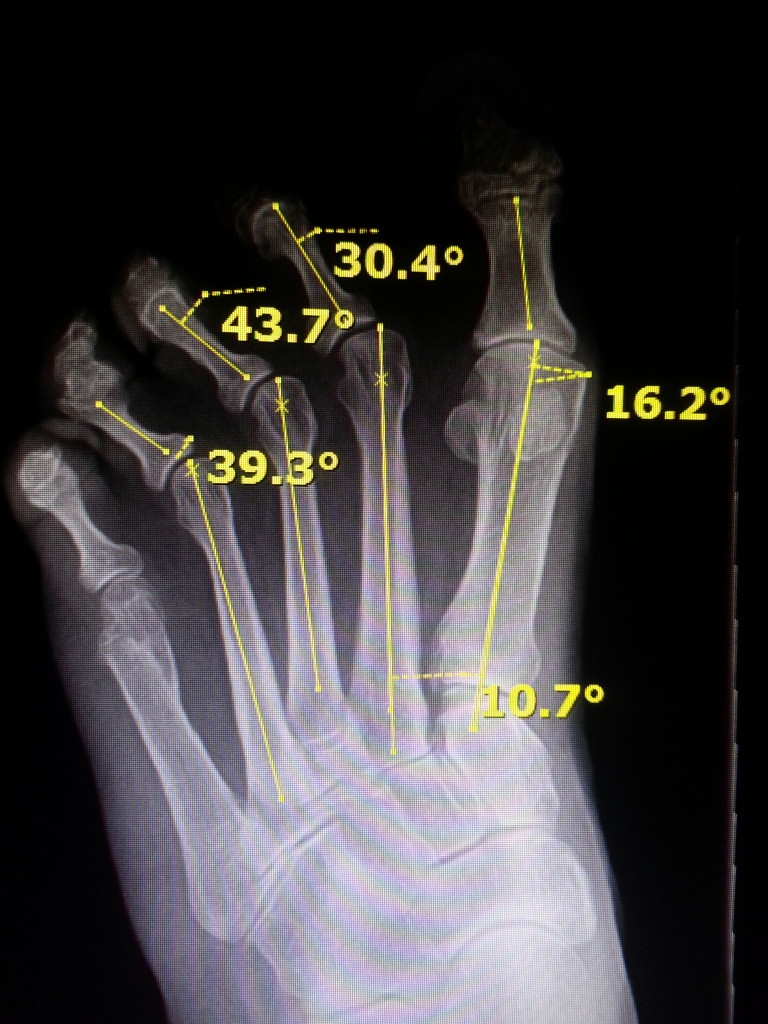

Plantar Pressure Distribution Before and After Surgery for Lesser Foot Joint Dislocation Treatment a joint dislocation is a complete separation of 2 articulating bony surfaces, often caused by a sudden impact to the joint. it typically involves the dislocation of one or more joints in the foot, resulting in pain, instability, and impaired. if there are no fractures or dislocations in the joint and the ligaments are not completely torn,. Foot Joint Dislocation Treatment.